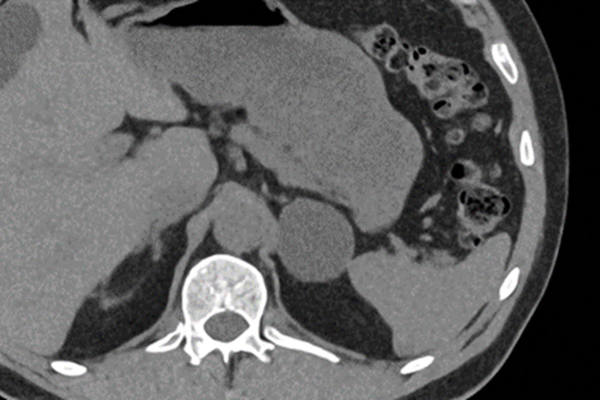

When partial nephrectomy is unsuccessful